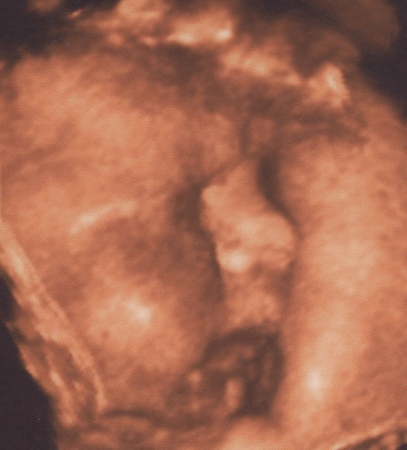

Kis tömzsi,golyó fejű az én édes kisfiam! :P

Bdp:10,13 cm; ofd:11,63; hc:34,78; fl:7,1; ac:33,1

Egy kicsit rövid a lába,de hát mi sem vagyunk óriásiak! :P

Méhlepény II.fokban érett,elegendő magzatvíz.Fejjel lefelé van törökülésben.Jaaaj nagyon jó volt látni!....és amikor ránk mosolygott... :oops: :P

Nagyon tetszenek a képek. 4D tényleg olyan, mintha egy fénykép lenne, teljesen felismerhetőek a vonások! És szerencsétek is volt, hogy ilyen rendes babó, és megmutatta az arcocskáját. Most megint ott vagyok, hogy nem baj, ha pici, de én MOST szeretném picikémet nézegetni!

Peti baba olyan jól látszik a képeken! :) Tényleg szerencsétek volt, hogy mindenét meg tudtátok nézni! Na, és a súlyáról nem írtál! Vagy csak én olvastam felületesen? Buksinak sincs hűű de hosszú lába, neki 6,95 mm-t mértek! :D És már csak 2-t kell aludni és itthon van Hábi!!!

a képek nagyon szépek :wink: Nagyon szépen látni Peti baba arcát :D